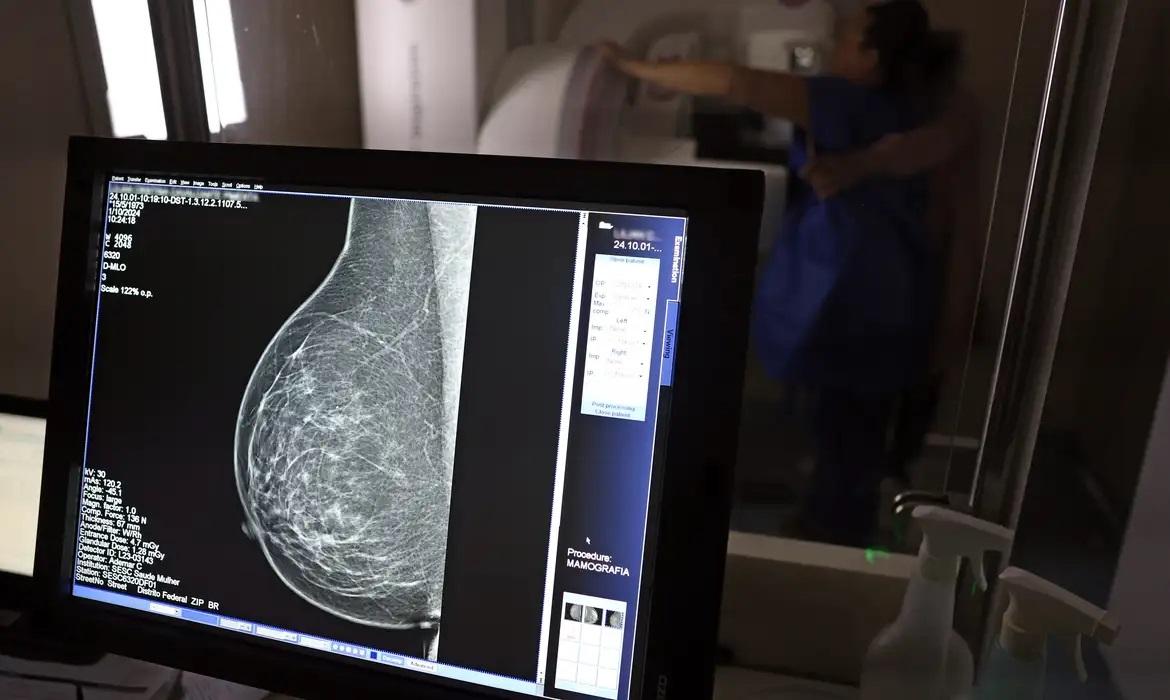

O Reino Unido aprovou o uso de um novo medicamento em certas pacientes que ajuda a retardar a propagação de um tipo incurável de câncer de mama, anunciaram as autoridades na sexta-feira, 11. O medicamento Truqap, desenvolvido pela farmacêutica britânica AstraZeneca, será oferecido a mulheres com câncer de mama hormônio-dependente do tipo HR+/HER2- quando a doença estiver disseminada e apresentar certas mutações genéticas.

Testado em pouco mais de 700 mulheres, este medicamento combinado com terapia hormonal (fulvestrant) estendeu o tempo de progressão do câncer de 3,6 para 7,3 meses. Também reduziu o tamanho do tumor em quase um quarto das pacientes.